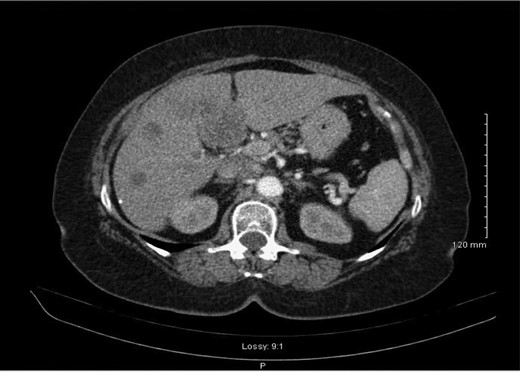

Histology demonstrated a 2.5 cm opaque stone and small cell undifferentiated carcinoma with tumour present in all layers of the gallbladder and lympho-vascular structures with invasion into the liver parenchyma. A subsequent staging computerized tomographic (CT) thorax, abdomen and pelvis demonstrated involvement of the lymph nodes within the coeliac axis and the porta hepatis, 3 mm nodular density in the right upper lobe of the lung and evidence of a metastatic deposit in the medial segment of the left hepatic lobe (Fig. 2). However, her completion staging CT brain revealed normal appearance.

Abdominal CT scan demonstrating metastasis to medial segment of left hepatic lobe.